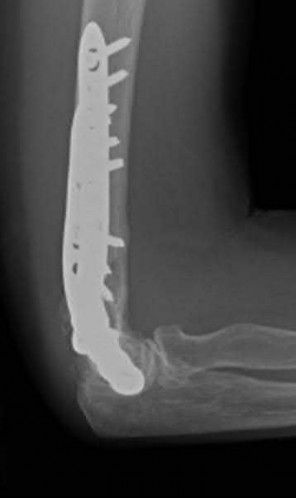

A 55-year-old patient presents with a slowly enlarging, painful mass in the proximal humerus.

Biopsy reveals a hyaline cartilage matrix with cellular atypia, confirming a diagnosis of central conventional chondrosarcoma. Which of the following genetic mutations is most frequently identified in this specific tumor?

Explanation

Mutations in the isocitrate dehydrogenase genes, IDH1 and IDH2, are found in up to 50-60% of central conventional chondrosarcomas and enchondromas. EXT1 and EXT2 mutations are characteristic of multiple hereditary exostoses (osteochondromas). GNAS mutations are seen in fibrous dysplasia. TP53 and RB1 mutations are hallmark aberrations in osteosarcoma.